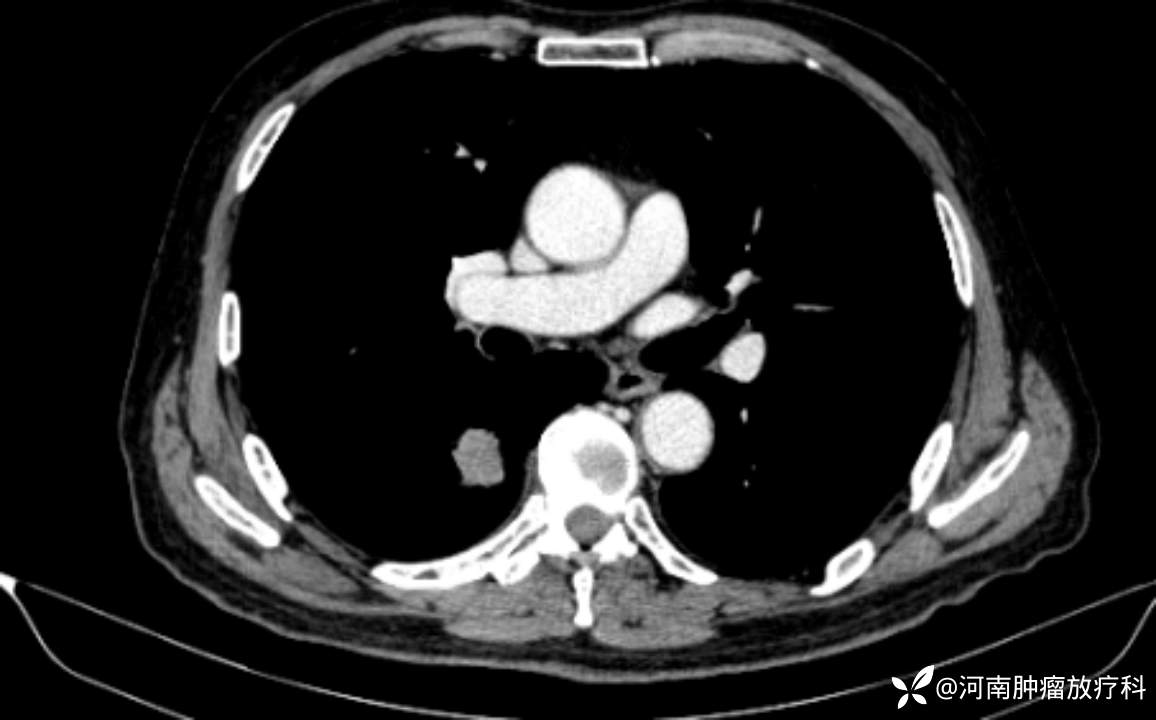

2022-9-23CT